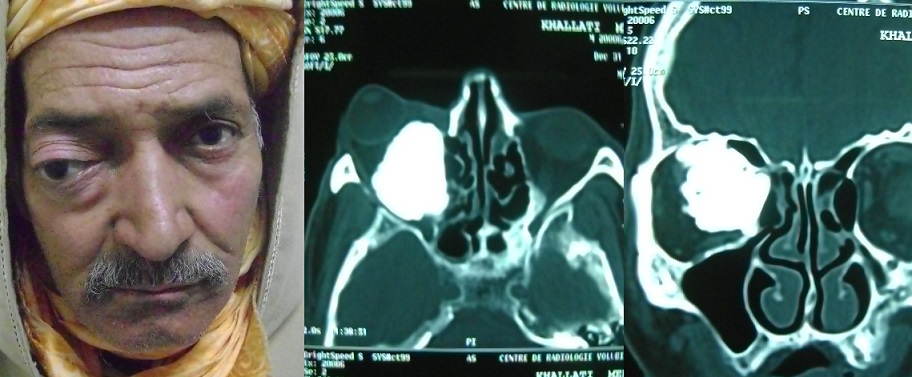

Un volumineux ostéome orbitaire : à propos d’un cas

L’ostéome orbitaire est une tumeur osseuse bénigne rare, communément asymptomatique et souvent de découverte radiologique fortuite. Nous rapportons le cas d’un ostéome orbitaire avec perte fonctionnelle de l’œil.